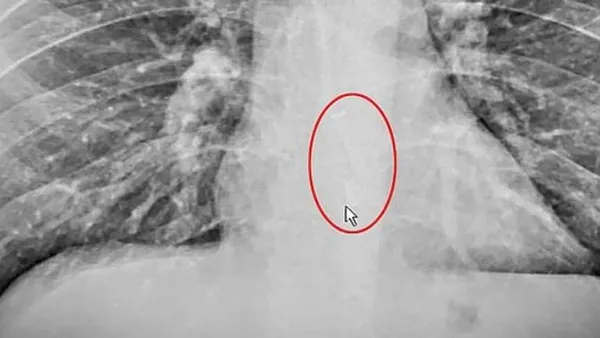

ABD'de Brad Gauthier (38) adlı kişi uykusunda akıllı telefon üreten ünlü bir teknoloji şirketine ait kablosuz kulaklığı yuttu. Kulaklık, endoskopi işlemiyle Gauthier'in yemek borusundan çıkarıldı.

Boğazında bir tıkanıklık hissettiğini belirten Gauthier, su içmeye çalıştığını ancak az kalsın boğulduğunu ifade etti. Hastaneye kaldırılan Gauthier'in yemek borusuna akıllı telefon üreten ünlü bir şirkete ait kablosuz kulaklığın takıldığı ortaya çıktı.

Gauthier'in yemek borusuna takılan kablosuz kulaklık, hastanede yapılan endoskopi işlemiyle çıkarıldı.